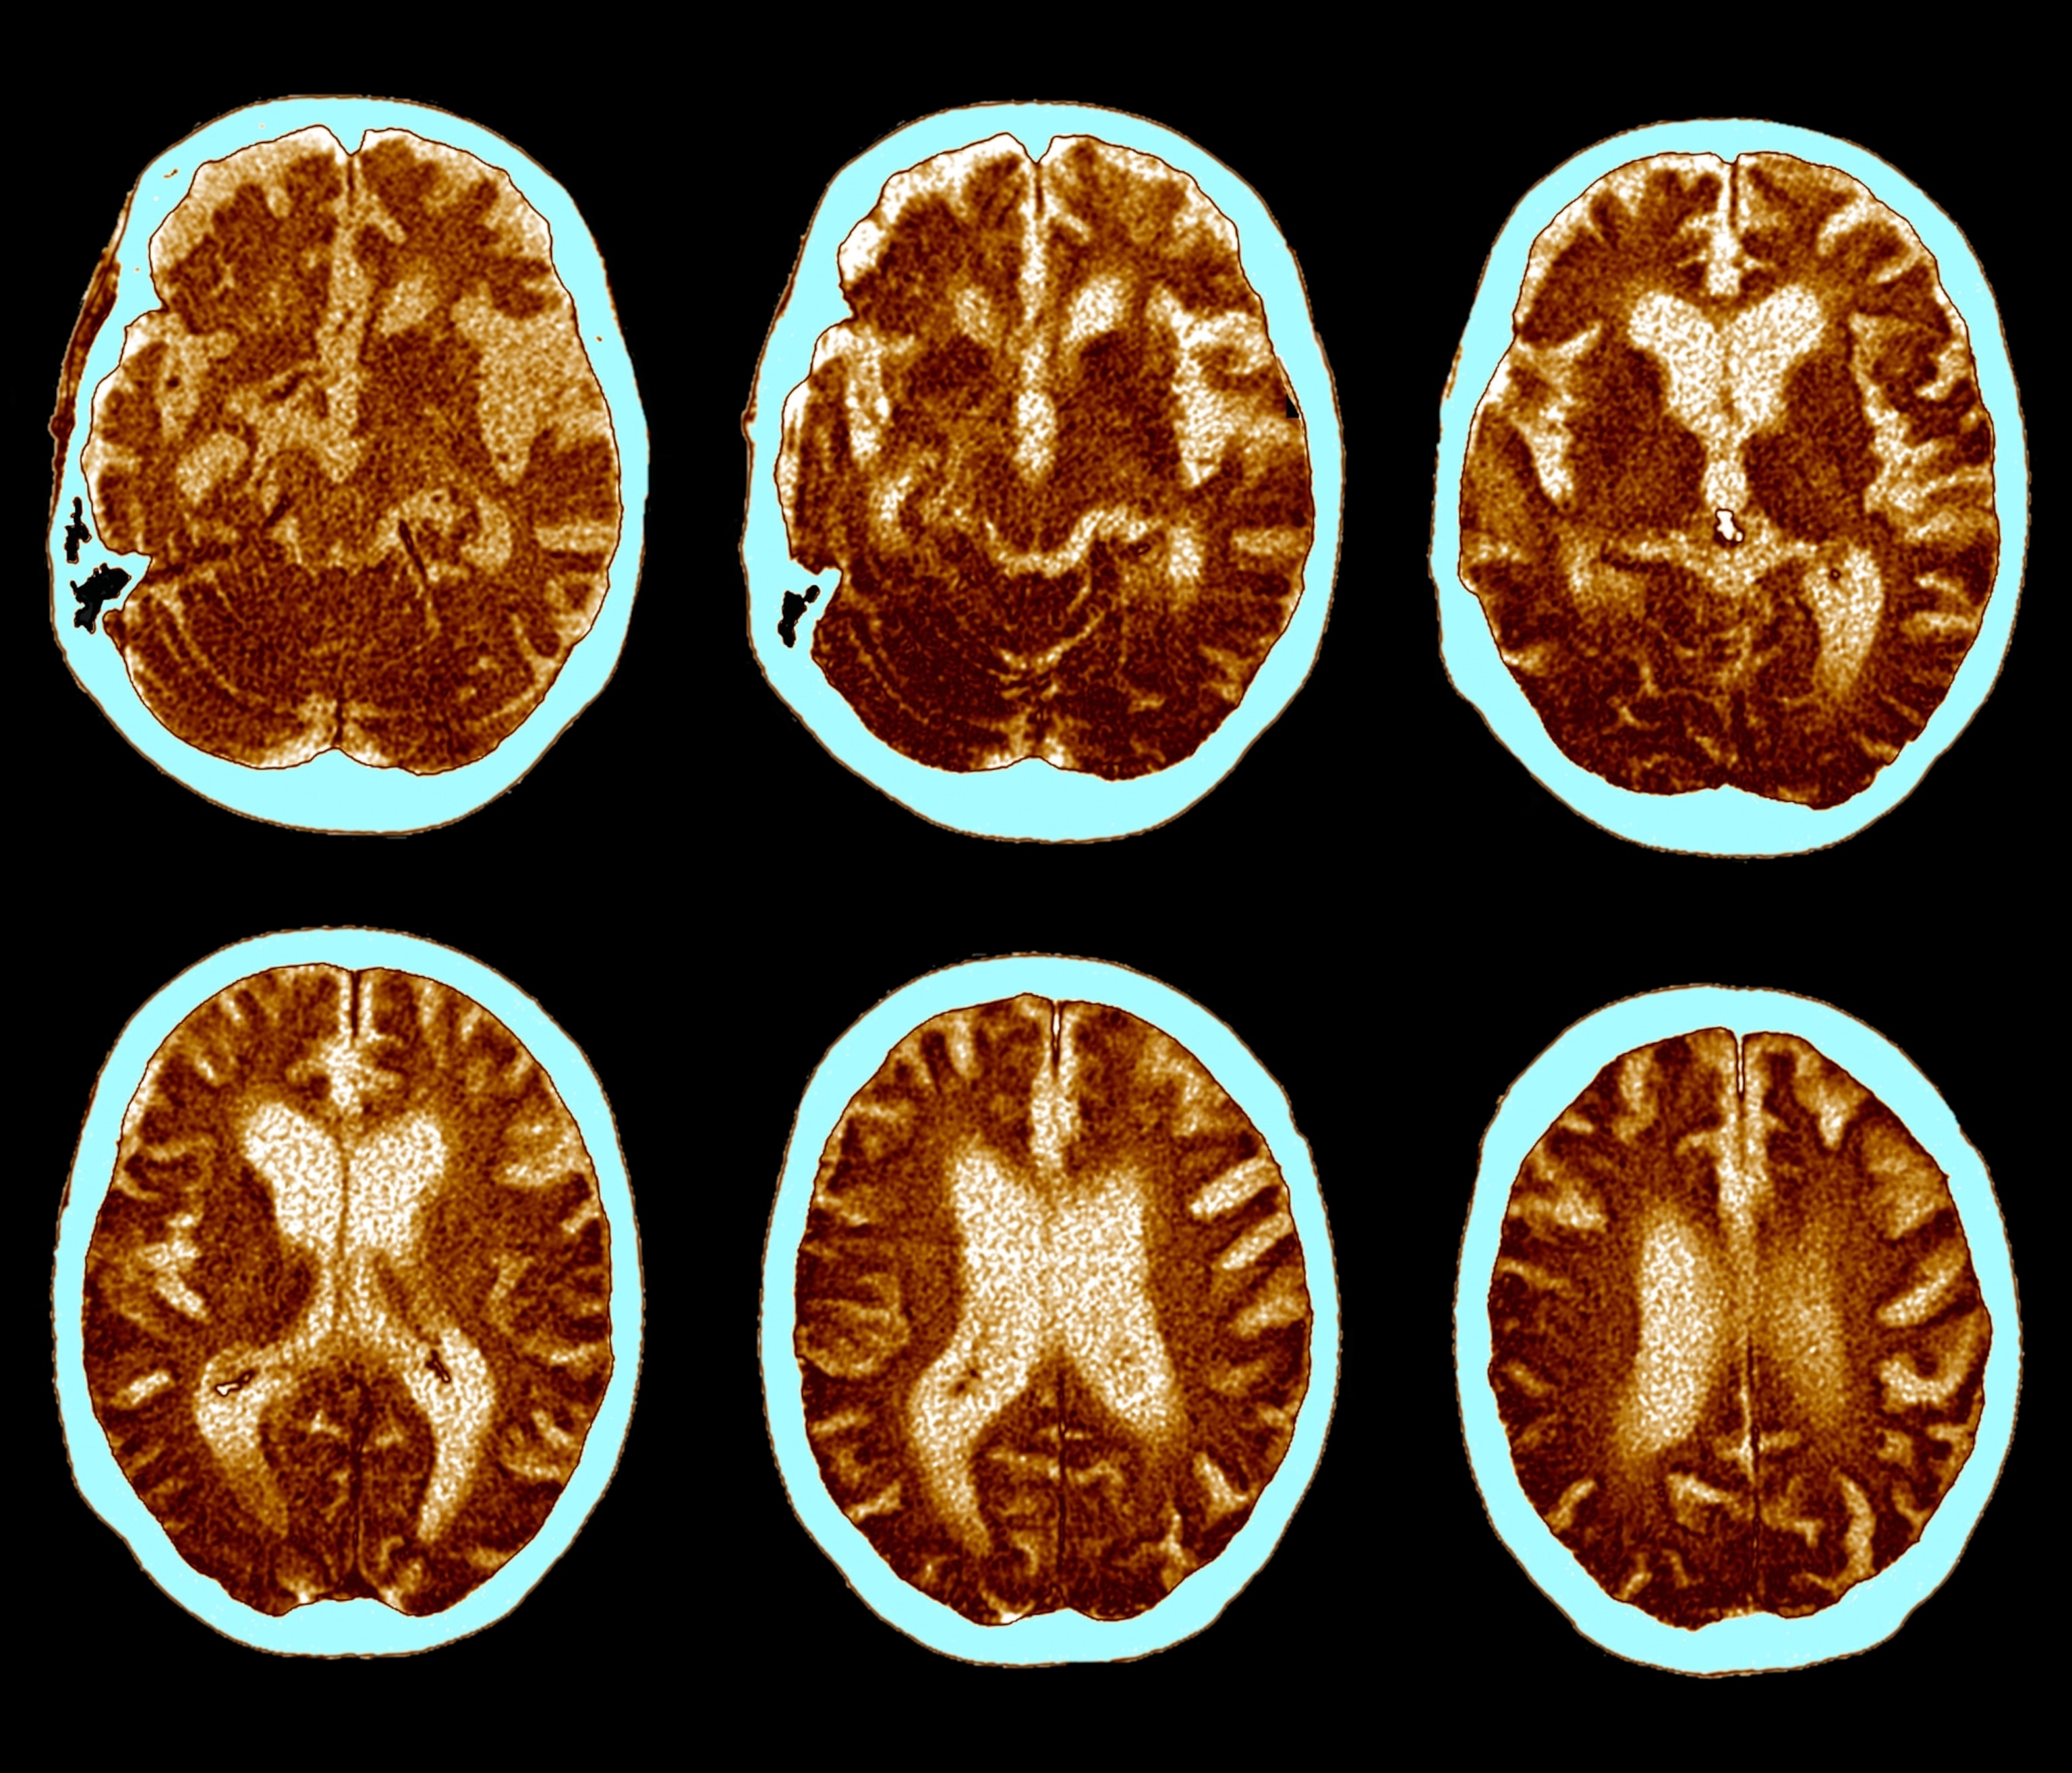

It certainly has always seemed to be. The defining feature of Alzheimer's—the most common form of dementia, affecting millions of people worldwide—is the buildup of proteins that cause amyloid plaques and tau tangles in the brain. This buildup is then followed by the death of neurons, which causes memory loss, mood disturbances, and behavioral changes.

For years, Alzheimer’s researchers primarily focused on the characteristic amyloid plaques, convinced that they were the primary cause of the disease. However, as research is showing, these plaques aren’t necessarily harmful in and of themselves, but rather, it’s the immune system’s response to the plaques that damages neurons.

“Some people get Alzheimer's in their 50s, some get it in their 90s, and some people pass away with more amyloid [plaques] in their brain than either of those, and they never develop the disease,” Schulze says. “The hypothesis is that amyloid and tau protein in the brain don’t directly cause neuronal damage, they cause it when your immune system reacts to them.”

As a result, researchers and clinicians are starting to think of Alzheimer's disease as a “disease of dysregulated brain immunity,” Weiss says.